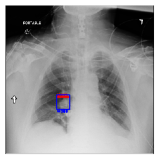

IV-D Investigation of the generated heatmap

By using the training result of the Adaptive DBN, the heatmap images were generated in addition to detection of B-Box. The heatmaps in Fig. 10 to Fig. 14 show the detection result of B-Box and the generated heatmap for some images. The red and blue rectangles in the image are given B-Box and detected B-Box, respectively. A heatmap is represented by the continuous value of range [0,255]0255[0,255], where the color map is jet color array (red means high value, while blue means small value). The diseases for detected B-Boxes in Fig. 10 to Fig. 14 were as follows; Infiltration (Fig. 10), Mass (Fig. 10), Nodule (Fig. 10), Mass and Pneumothorax (Fig. 10), Atelectasis (Fig. 14), Infiltration (Fig. 14), Atelectasis (Fig. 14), Atelectasis (Fig. 14).

Overall, the red area of the generated heatmap included in both the given B-Box and detected B-Box. On the other hand, the blue or yellow areas didn’t include in these B-Boxes. This tendency was seen in not only large diseases (e.g. Cardiomegaly or Infiltration) such as Fig. 10, but also small diseases (e.g. Mass or Nodule) such as Fig. 10. We consider that the experimental results caused by the discrete heatmap with binary output of final RBM layer instead of continuous heatmap. As a result, the red regions represents localization with strong relation to diseases and blue regions represents localization with weak relation. The generated heatmap shows the portion with strong relation more clearly.

In Fig. 14, the detected B-Box was located at a little upper than the given B-Box. The red area of the heatmap was also at upper position. The detected B-Box is slightly larger than the given B-Box. The detected B-Boxes are almost same as the given B-Boxes except the different size. For better detection capability, the feature of the generated heatmap will be investigated with the medical specialists.